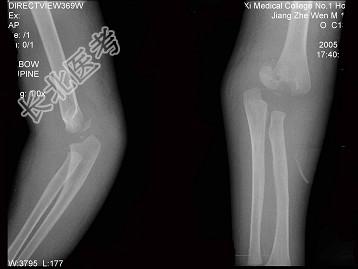

- 单项选择题女,1岁10个月, 右肘部外伤,如图所示, 最佳的诊断为 ( )

A、全骺分离

B、肱骨髁上骨折

C、肱骨髁上骨折并肘关节脱位

D、内上髁骨骺损伤

E、内上髁骨骺损伤并肘关节脱位